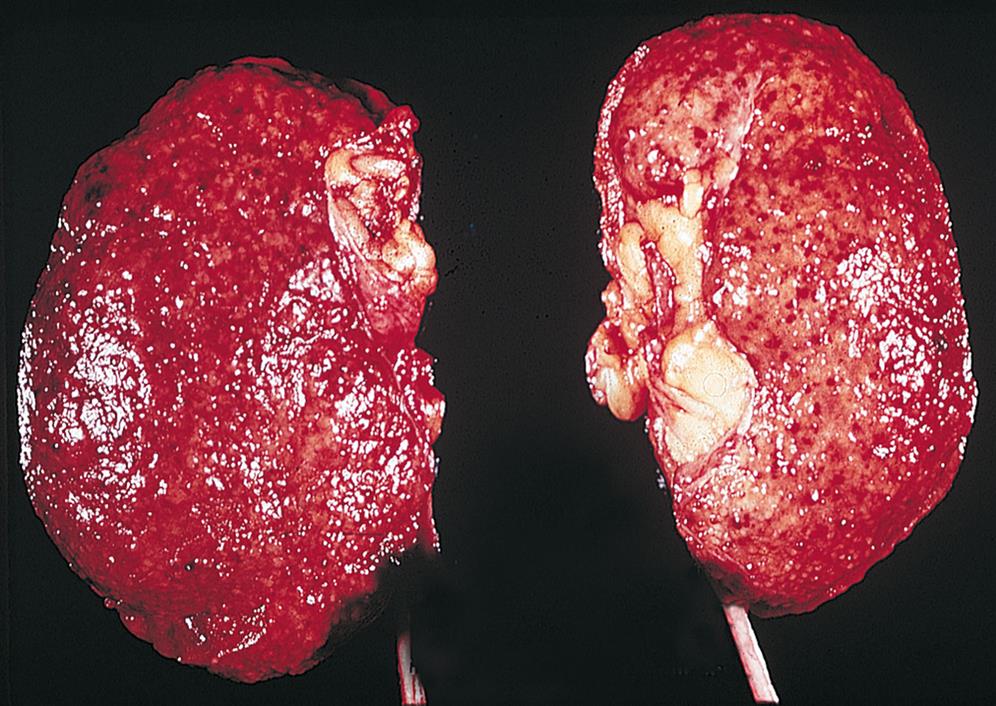

There are several different types of RCCs. They are classified according to subtypes and extent of metastasis. Clear cell RCC is the most common renal neoplasm (80% of all renal neoplasms) and represents about 2% of cancer deaths.32,33 It occurs primarily in the proximal tubule of the renal cortex. Other types include papillary (small fingerlike growths) and chromophobe RCC (larger cells), and both occur in the distal tubules of the kidneys.34 Confinement within the renal capsule, together with treatment, is associated with a better survival rate. The tumors usually occur unilaterally (Fig. 38.3). Renal transitional cell carcinoma (RTCC) is rare and primarily arises in the renal parenchyma and renal pelvis near the ureteral orifice. Renal adenomas (benign tumors) are uncommon but are increasing in number. The tumors are encapsulated and are usually located near the cortex of the kidney. Some tumors are unclassified because they have multiple cell types. Because the tumors can become malignant, they are usually surgically removed.

Chronic urinary tract obstruction prevents elimination of bacteria and starts a process of progressive inflammation. Alterations occur within the renal pelvis and calyces from the obstruction and inflammation (Fig. 38.6). There is destruction of the tubules and diffuse scarring, which impairs urine-concentrating ability. The lesions of chronic pyelonephritis are sometimes termed chronic interstitial nephritis because the inflammation and fibrosis are located in the interstitial spaces between the tubules.